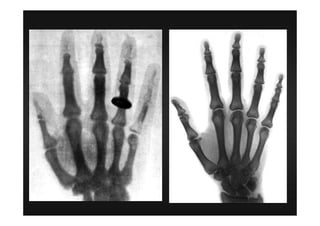

Roentgen 1895

1a observação do R X (observou

sem conseguir explicar).

Aparelho que causava emissão de R X

Papelão revestido por produtos

químicos

Papelão fluorescente

Forma de energia radiante e invisível no

qual podiam causar florescência e

atravessar materiais opacos a luz

Raio X

SALA ESCURA

Aparelho que emite raio X

Mão

Papelão florescente

Imagem da mão em positivo

Papel fica mais branco onde

chega mais raio X

Mais branco = mais

fluorescente

Mais negro = pouca reação

do papelão

figura

1901 1o premio